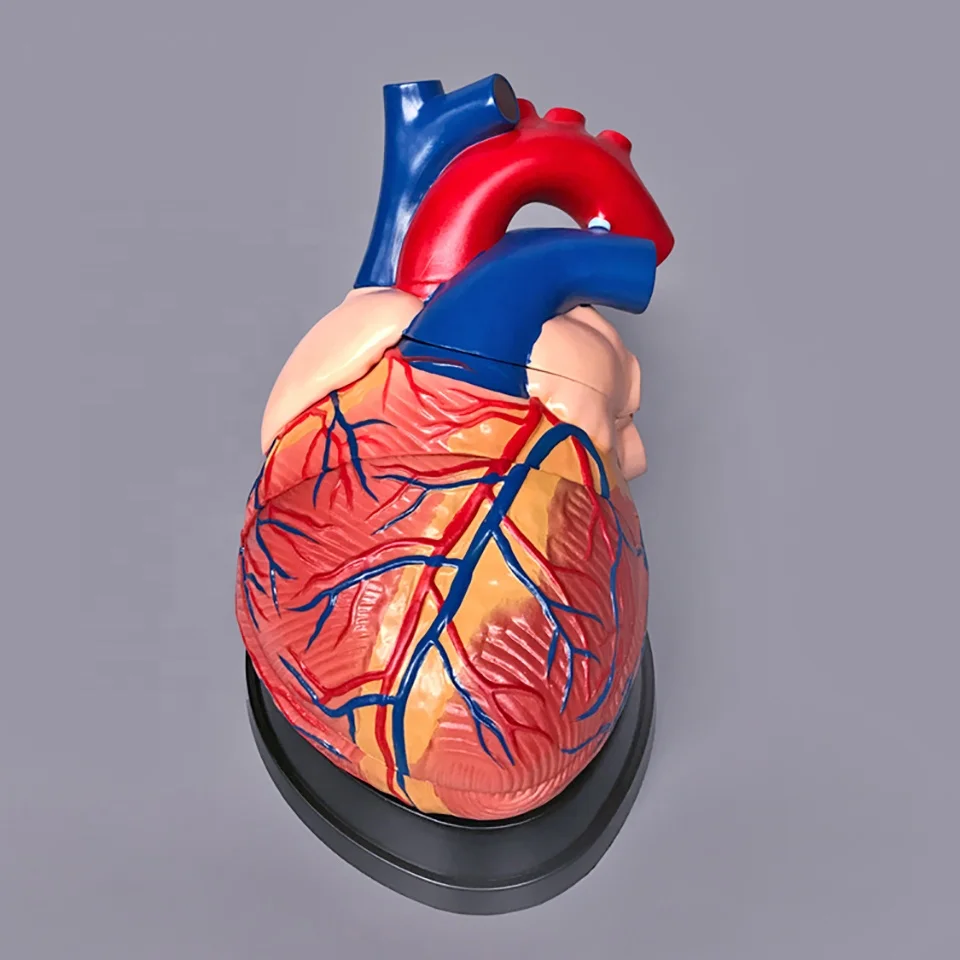

ขยายกายวิภาคหัวใจมนุษย์รุ่น 3 ชิ้นส่วน – Buy กายวิภาคหัวใจ,หัวใจ … หัวใจมนุษย์ การออกแบบรายละเอียด ภาพประกอบสต็อก – ดาวน์โหลดรูปภาพตอนนี้ …

ชีวิตพลาสติกกายวิภาคหัวใจมนุษย์รุ่น2ชิ้นส่วน – Buy การสอนรุ่น,Anatomy … ช็อคโกแลตรูปหัวใจ [ภาพวาดฟรี] | OkusanPix

หัวใจวิทยาศาสตร์เรื่องกายวิภาคศาสตร์ทางการแพทย์หัวใจมนุษย์รุ่นขาย – Buy … รูปเวกเตอร์ฟรีหัวใจการ์ตูนปุ่ม PNG , หัวใจมนุษย์, หัวใจ, เซลล์ภาพ PNG …

ชีวิตพลาสติกกายวิภาคหัวใจมนุษย์รุ่น2ชิ้นส่วน – Buy การสอนรุ่น,Anatomy … ขนมช็อกโกแลตแท่ง ตรา โชกี้ โชกี้ 1 บาท แพ็ค 100 ชิ้น | Shopee Thailand

ขนมช็อกโกแลตแท่ง ตรา โชกี้ โชกี้ 1 บาท แพ็ค 100 ชิ้น | Shopee Thailand ชีวิตพลาสติกกายวิภาคหัวใจมนุษย์รุ่น2ชิ้นส่วน – Buy การสอนรุ่น,Anatomy …

ชีวิตพลาสติกกายวิภาคหัวใจมนุษย์รุ่น2ชิ้นส่วน – Buy การสอนรุ่น,Anatomy … รักสุดใจ! ช่อช็อกโกแลตให้เธอ รวมไอเดียช่อช็อกโกแลตสื่อรัก มอบให้แฟน

รักสุดใจ! ช่อช็อกโกแลตให้เธอ รวมไอเดียช่อช็อกโกแลตสื่อรัก มอบให้แฟน แบบจำลองหัวใจมนุษย์ขนาดชีวิตที่มีสีพื้นโปร่งใสโรคหัวใจทางการแพทย์แบบ …

แบบจำลองหัวใจมนุษย์ขนาดชีวิตที่มีสีพื้นโปร่งใสโรคหัวใจทางการแพทย์แบบ … Chocolate Heart, Hand-drawn sketch Chocolate s, brown, food png | PNGEgg

Chocolate Heart, Hand-drawn sketch Chocolate s, brown, food png | PNGEgg แบบจำลองหัวใจมนุษย์ขนาดชีวิตที่มีสีพื้นโปร่งใสโรคหัวใจทางการแพทย์แบบ …

แบบจำลองหัวใจมนุษย์ขนาดชีวิตที่มีสีพื้นโปร่งใสโรคหัวใจทางการแพทย์แบบ … ช็อกโกแลต รูปฟุตบอล เหรียญทอง หัวใจ บรรจุ 60 ชิ้น | Shopee Thailand

In-306 3d กายวิภาคศาสตร์หัวใจมนุษย์รูปแบบทางการแพทย์พลาสติกกายวิภาค … หัวใจมนุษย์ ภาพสต็อก – ดาวน์โหลดรูปภาพตอนนี้ – หัวใจ – อวัยวะภายใน, การ …

หัวใจวิทยาศาสตร์เรื่องกายวิภาคศาสตร์ทางการแพทย์หัวใจมนุษย์รุ่นขาย – Buy … หัวใจวิทยาศาสตร์เรื่องกายวิภาคศาสตร์ทางการแพทย์หัวใจมนุษย์รุ่นขาย – Buy …

หัวใจวิทยาศาสตร์เรื่องกายวิภาคศาสตร์ทางการแพทย์หัวใจมนุษย์รุ่นขาย – Buy … Anatomy หัวใจมนุษย์รุ่นพลาสติกทางการแพทย์กายวิภาคหัวใจจัมโบ้รุ่นอวัยวะ …

Anatomy หัวใจมนุษย์รุ่นพลาสติกทางการแพทย์กายวิภาคหัวใจจัมโบ้รุ่นอวัยวะ … รูปช็อกโกแลตหัวใจพร้อมน้ำเชื่อม PNG , วาเลนไทน์วัน, หัวใจ, วันแห่งความ …

3d Anatomy หัวใจมนุษย์รุ่นพลาสติกทางการแพทย์กายวิภาคหัวใจจัมโบ้รุ่น … หัวใจวิทยาศาสตร์เรื่องกายวิภาคศาสตร์ทางการแพทย์หัวใจมนุษย์รุ่นขาย – Buy …

หัวใจวิทยาศาสตร์เรื่องกายวิภาคศาสตร์ทางการแพทย์หัวใจมนุษย์รุ่นขาย – Buy … ส่งไว🚀24ชม. เจบีช็อกโกแลต รูปฟุตบอล เหรียญทอง เหรียญเงิน ทองแท่ง หัวใจ …

ส่งไว🚀24ชม. เจบีช็อกโกแลต รูปฟุตบอล เหรียญทอง เหรียญเงิน ทองแท่ง หัวใจ … Anatomy หัวใจมนุษย์รุ่นพลาสติกทางการแพทย์กายวิภาคหัวใจจัมโบ้รุ่นอวัยวะ …

Anatomy หัวใจมนุษย์รุ่นพลาสติกทางการแพทย์กายวิภาคหัวใจจัมโบ้รุ่นอวัยวะ … ภาพประกอบแบนเวกเตอร์หัวใจมนุษย์ขนาดใหญ่บนพื้นหลังสีขาว ภาพประกอบสต็อก …

หัวใจมนุษย์กายวิภาครุ่นวิทยาศาสตร์การแพทย์รูปแบบการสอน ห้องหัวใจมนุษย์: คำอธิบายโครงสร้างหน้าที่และประเภท

หุ่นจำลองหัวใจมนุษย์ 3d มนุษย์กายวิภาครุ่นหัวใจมนุษย์สำหรับซัพพลายเออร์แบบครบวงจรวิทยาศาสตร์ …

3d มนุษย์กายวิภาครุ่นหัวใจมนุษย์สำหรับซัพพลายเออร์แบบครบวงจรวิทยาศาสตร์ … 3d Anatomy หัวใจมนุษย์รุ่นพลาสติกทางการแพทย์กายวิภาคหัวใจจัมโบ้รุ่น …

3d Anatomy หัวใจมนุษย์รุ่นพลาสติกทางการแพทย์กายวิภาคหัวใจจัมโบ้รุ่น … อวัยวะหัวใจของมนุษย์ | องค์ประกอบกราฟฟิก แบบ PSD ดาวน์โหลดฟรี – Pikbest

หัวใจมนุษย์กายวิภาครุ่นวิทยาศาสตร์การแพทย์รูปแบบการสอน 15 Porch ช็อกโกแลต Fudge แม่พิมพ์ซิลิโคนหัวใจรูปเค้กช็อกโกแลตตกแต่ง DIY …

อุปกรณ์การศึกษากายวิภาคศาสตร์รุ่นหัวใจมนุษย์รุ่นสำหรับโรงเรียนขนาดชีวิต … วิธีทำ “นามะช็อกโกแลต” ของฝากยอดฮิตจากญี่ปุ่น อร่อยหรูดูแพง แต่ทำง่าย …

โรงงานโดยตรงขาย Anatomy หัวใจมนุษย์การฝึกอบรมชุดอวัยวะภายในรุ่น – Buy …